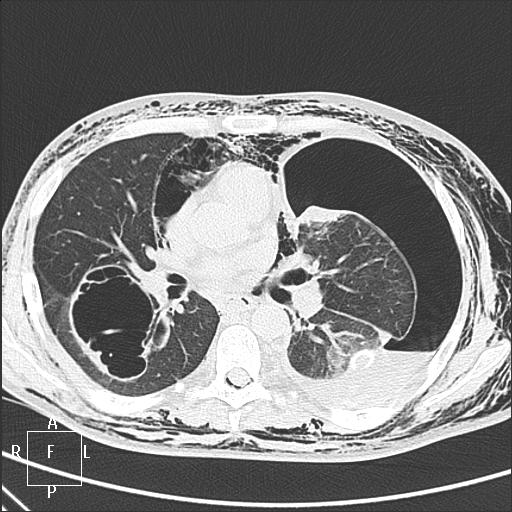

Мужчина, 31 год. ВИЧ+, на учёте 1,5 года, прекратил употреблять наркотические средства около года назад, получает специфическое противовирусное лечение. Носитель гепатита С (обострение в марте, хотели после лечения выписать, но вдруг затемпературил). Динамика с 23 марта по 18 апреля. Состояние с 8 апреля оценивается как тяжелое, боковые снимки с динамической нерезкостью.

КТ от 18.04:

Норма в марте (с усилением рисунка в базальных отделах справа без предыдущих снимков можно поспорить). Затем абсцедирующая пневмония в S6 справа и S8-9-10 слева. Затем напряженный пневмоторакс слева с малым|средним гидротораксом. На контроле левое легкое частично расправлено, уровень жидкости до 6 ребра по задней подмышечной линии. Последний - больших размеров пневмоторакс слева, выраженная эмфизема мягких тканей и пневмомедиастинум.

После контроля 18 апреля взяла на КТ. Изображения в начале темы. Есть вопрос: подскажите, пожалуйста, каким анатомическим путём воздух попал в эпидуральное пространство?